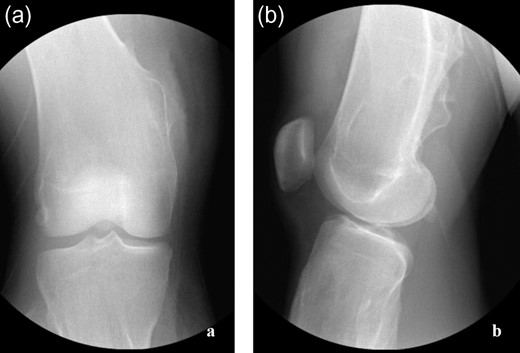

The procedure began with examination under anesthesia—the right leg could be forcefully extended but resulted in significant tension about the posteromedial soft tissues of the leg. The limb was circumferentially prepped and draped in the standard orthopedic fashion without the use of a tourniquet. The osteochondromas were localized (Fig. 2a–c) and exploration revealed a bursa superficial to the osteochondroma. The gracilis tendon was in its appropriate anatomic position cranial to the pedunculated osteochondroma. The semitendinosus tendon was incarcerated inferior to the osteochondroma (Fig. 3a), creating the locked knee effect. The hooked tendon was protected, and the 3 cm osteochondroma (Fig. 3b) was removed with an oscillating saw, freeing the entrapped tendon and restoring normal movement of her knee. Radiographic imaging (Fig. 4a and b) confirmed satisfactory removal of the lesions, and the wounds were closed. At the 3-month follow-up, the patient had returned to all desired activities with no recurrent medial knee pain or locking.

(a and b) Post-operative radiographs confirming adequate lesion excision about proximal tibia and distal femur.